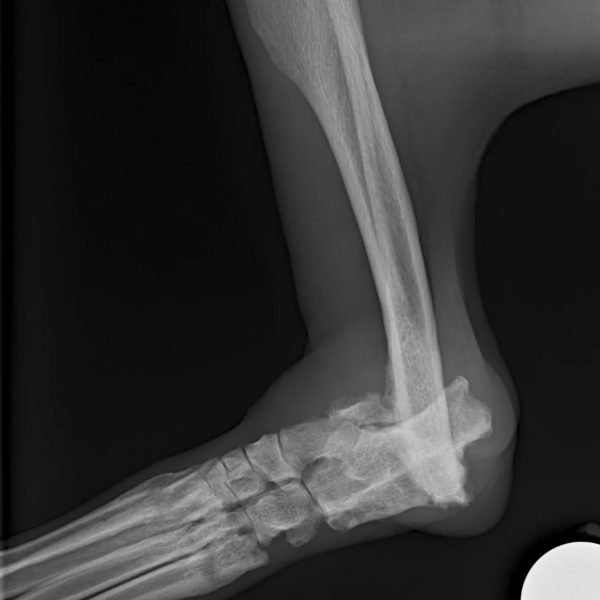

Wir fanden Sam heuer in Rumänien in einem kleinen, dunklen Zwinger. Sein Hinterbein baumelte so irgendwie rum

. Schnell war uns klar, wir müssen diesem armen Kerl helfen.

Nach eingehenden Untersuchungen und Telefonaten mit Chirurgen und Orthopäden haben wir für den 21.12.23 einen OP Termin in einer Speziaklinik in der Nähe von München für Sam ausgemacht.

Der alte Bruch wird verplattet werden und das Sprunggelenk versteift. Wir hoffen sehr, dass Sam im Anschluss endlich ein schmerzfreies Leben haben wird!